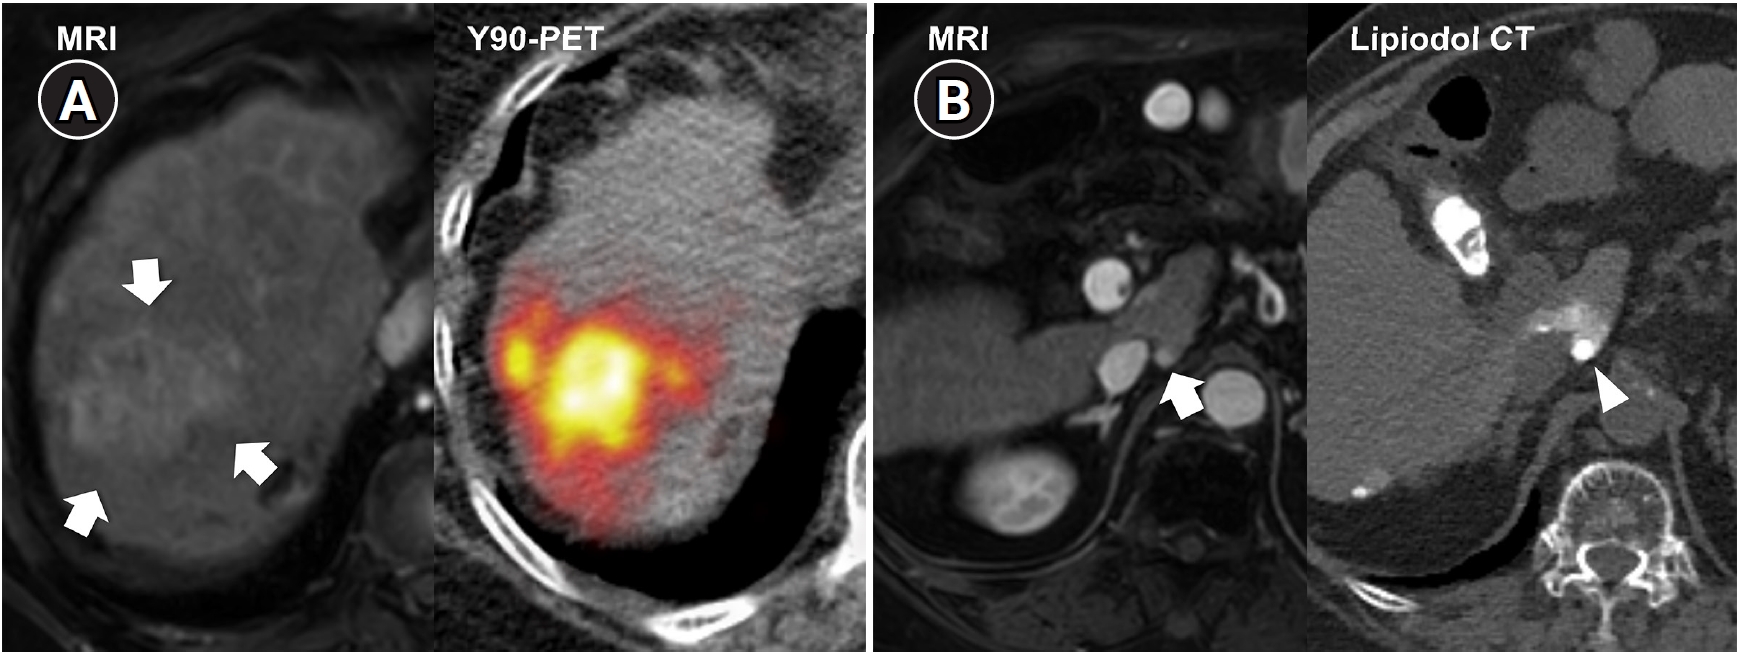

Fig. 2.

Radiation major hepatectomy in a 60-year-old woman with hepatocellular carcinoma. (A) Contrast-enhanced computed tomography (CT) shows a 9.0-cm hypervascular tumor (arrows) with two satellite nodules (not shown) in segments 7 and 8. (B) Cone-beam CT hepatic arteriography shows tumor staining (arrows) supplied by A7 and A8 (arrowheads). A total of 9.11 GBq of glass microspheres was infused via A7 and A8. (C) Post-treatment Y-90 positron emission tomography shows intense uptake throughout the tumor, consistent with complete microsphere coverage, with a perfused liver dose of 355.3 Gy and a tumor dose of 609.9 Gy. (D) Fifty-month follow-up CT shows complete response with dystrophic calcification (arrows), atrophy of segments 7 and 8, and compensatory hypertrophy of the left hepatic lobe (double arrowheads).

Fig. 2. Radiation major hepatectomy in a 60-year-old woman with hepatocellular carcinoma. (A) Contrast-enhanced computed tomography (CT) shows a 9.0-cm hypervascular tumor (arrows) with two satellite nodules (not shown) in segments 7 and 8. (B) Cone-beam CT hepatic arteriography shows tumor staining (arrows) supplied by A7 and A8 (arrowheads). A total of 9.11 GBq of glass microspheres was infused via A7 and A8. (C) Post-treatment Y-90 positron emission tomography shows intense uptake throughout the tumor, consistent with complete microsphere coverage, with a perfused liver dose of 355.3 Gy and a tumor dose of 609.9 Gy. (D) Fifty-month follow-up CT shows complete response with dystrophic calcification (arrows), atrophy of segments 7 and 8, and compensatory hypertrophy of the left hepatic lobe (double arrowheads).